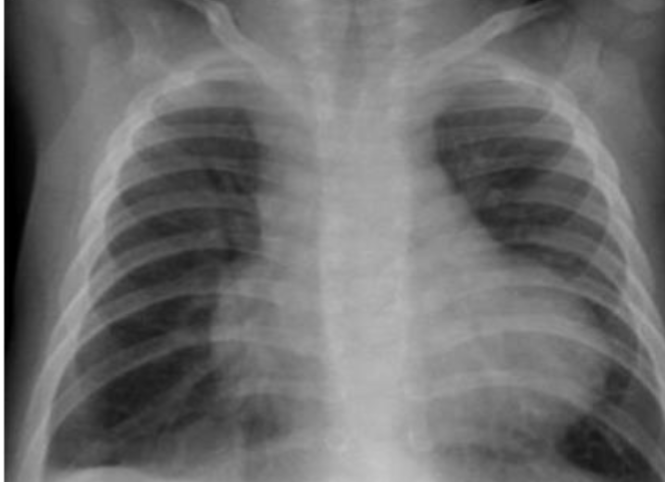

- AP chest film showing moderately increased heart size. Heart diameter to - (1 .trans-thoracic diameter ratio is 78 %. This is a cardiomegaly

- The cause is Congestive Heart Failure [CHF] secondary to viral - (2 .myocarditis